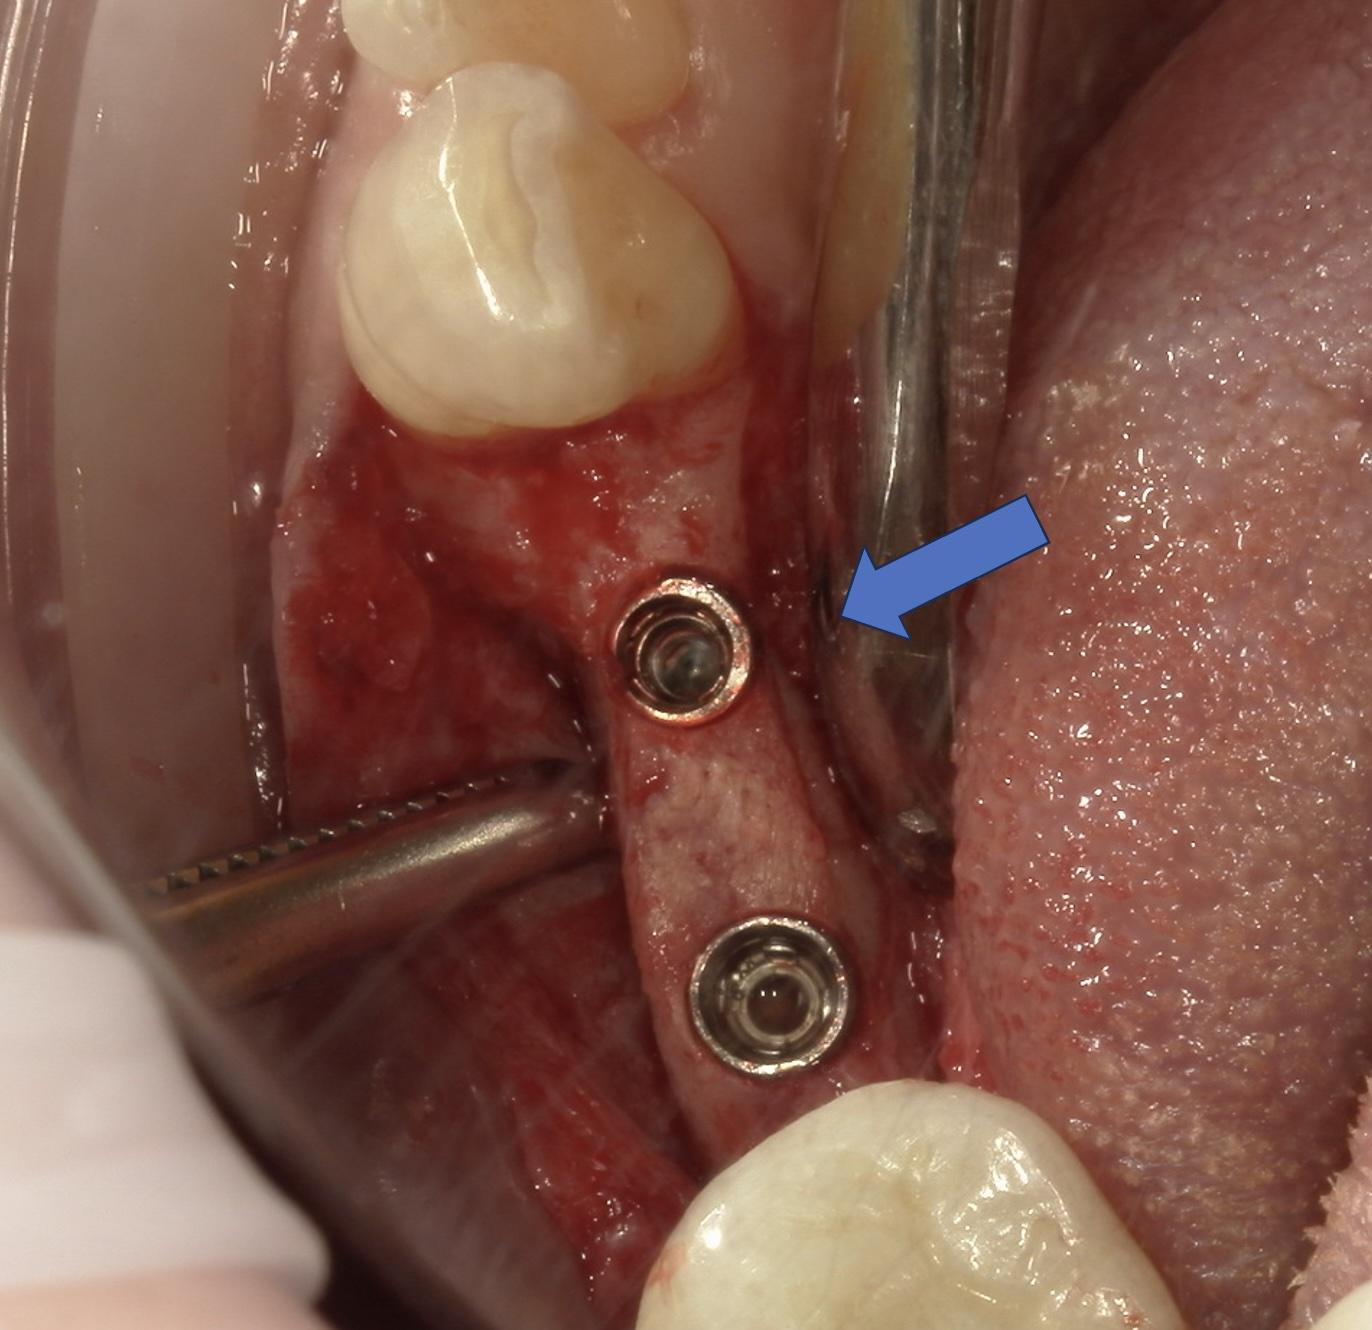

こんな細い下顎骨にインプラントを入れることが可能なのでしょうか?昔であれば、スプリットクレストといい骨を2枚に割ってインプラントを入れる手術をしたり、リッジエクスパンジョンとう骨を叩いて広げる手術をしてインプラントを入れたりしていましたが、患者さんの手術負担が大きくなる、手術料金が高くなる等のデメリットがありました。

そこで私は本ケースにストローマンのスモールクロスフィットという2.9mmの新しくて細いインプラントを適用しました。これを使うことにより、骨を割ったり叩いたりする必要は無くなり、手術負担も減ります。

ただ、細い骨にキレイにインプラントを入れるのは技術が必要となります。

今回はサージカルガイドを使って正確な埋入を行うことにより細い骨にキレイにインプラントを入れることができました。患者様の術後経過も良好です。